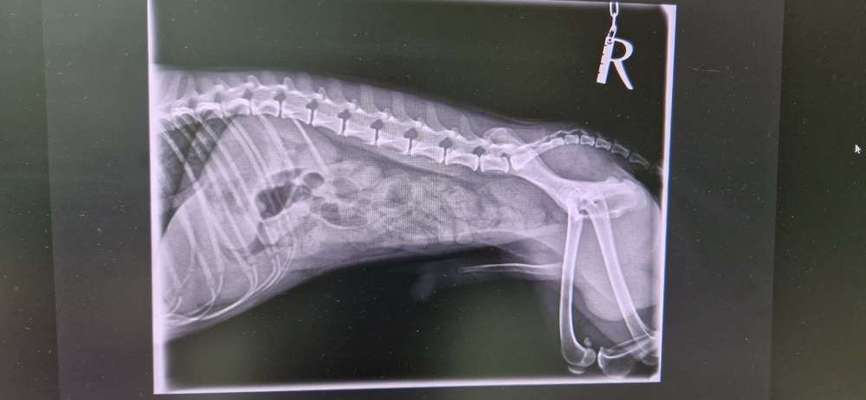

Wer kann mir helfen anhand der Bilder?? Mein kleiner flip hat sich nur noch erbrochen.

Er sagt Verstopfung, der kleine ist sei gestern abend in der tierklinik.

Wir drücken die Daumen das es der kleinen Fellnase schnell wieder besser geht. Hoffentlich keinen Darmverschluss. Und sie finden in der Tierklinik schnell die Ursache 🍀🍀🐕